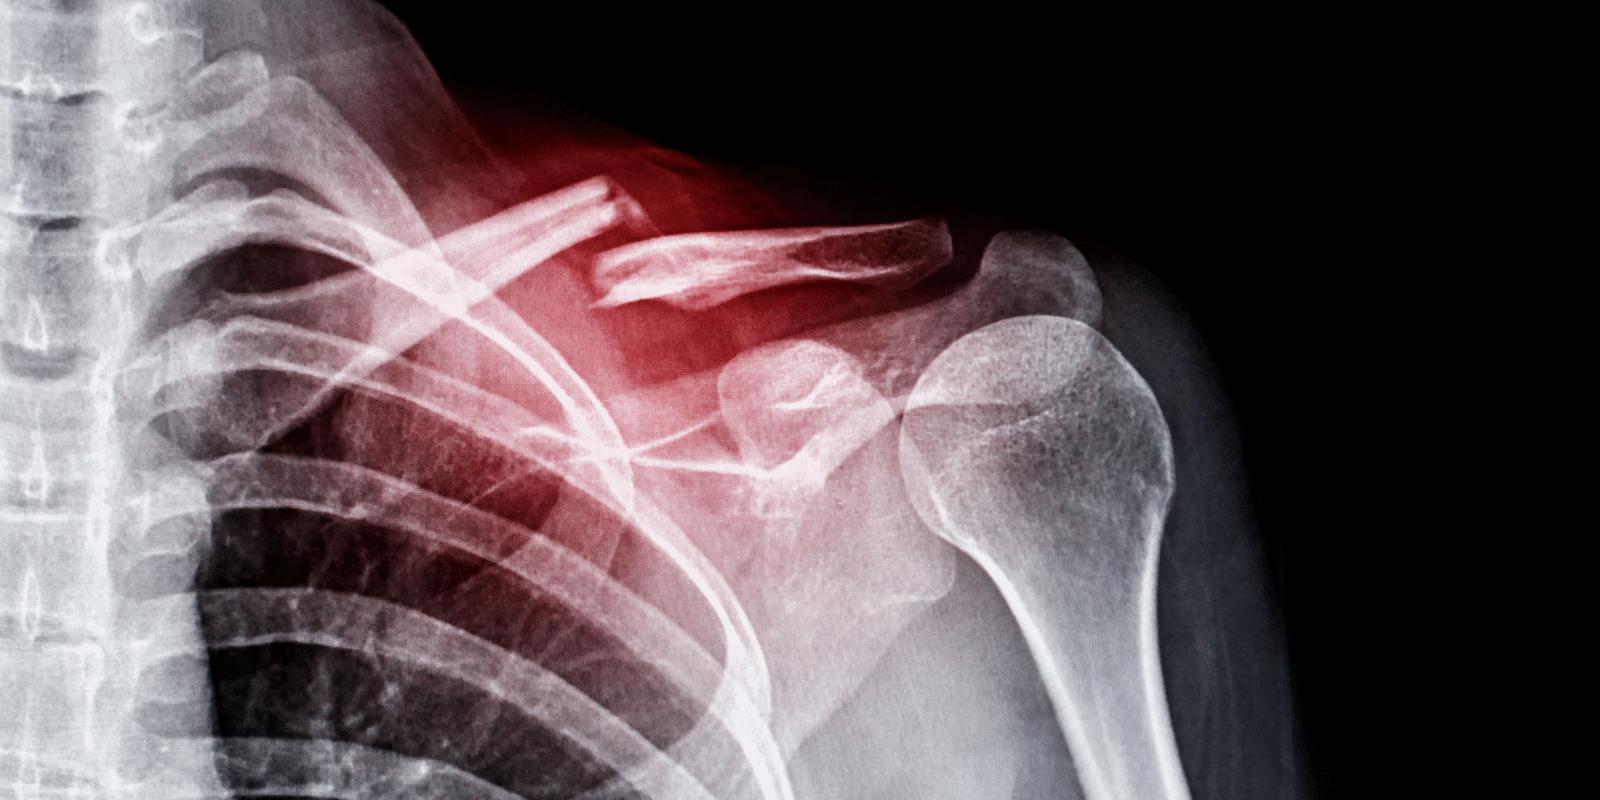

어깨뼈 골절과 통증기간

어깨뼈 골절은 교통사고, 스포츠 활동 중 또는 낙상으로 인해 발생할 수 있습니다. 통증의 정도와 기간은 골절의 심각성, 위치, 치료 방법에 따라 다양하게 나타납니다. 초기에는 골절 부위의 부기와 충격으로 인한 극심한 통증이 나타날 수 있으며, 병원에서 제공하는 진통제는 이러한 통증을 상당히 완화시켜줍니다. 골절된 뼈가 안정되고 치유 과정이 진행됨에 따라 통증은 점차 감소하게 됩니다. 대부분의 경우, 골절 직후 몇 주 안에 통증은 크게 줄어들며, 이후 재활 과정에서 관리할 수 있는 수준으로 조절됩니다.